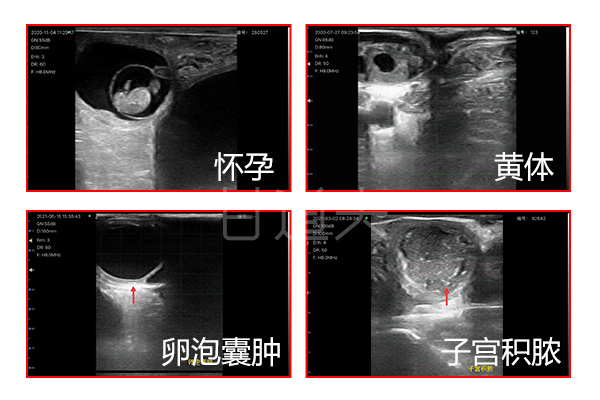

獸用無線智能B超是當前獸用超聲造影技術(shù)正引領(lǐng)第三次超聲革命,具有無線傳輸,高清成像,零延遲,體積輕巧,超長續(xù)航,信號穩(wěn)定,抗干擾能力強,經(jīng)久耐用等眾多優(yōu)勢,尤其在超高清的血流和組織圖像,幫助畜牧醫(yī)生更準確地診斷出老年動物可能面臨的心臟、腎臟、肝臟,卵巢,子宮等器官的疾病病變發(fā)展趨勢,能做到早發(fā)現(xiàn)早預防早干預,快速提升動物疾病防控能力和快速篩查出豬牛羊驢馬貓狗等動物發(fā)情和懷孕狀態(tài)胎子數(shù)量是否有死胎畸形心跳心率等生命特征,快速提升動物繁殖育種改良的能力。